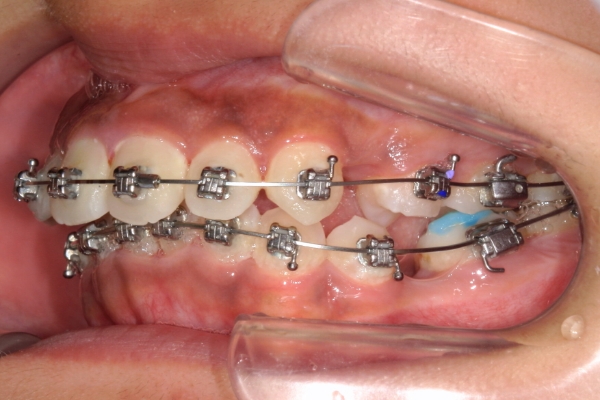

PROCESS

半年

上顎前歯が1 cm近く前方に出ており、叢生を改善しつつ前歯を大きく引っ込めるために上下顎小臼歯の抜歯が必要と診断しました。治療では奥歯の噛み合わせのズレも整え、治療後は前歯でも奥歯でも食べ物が噛みやすくなったと、患者さまに非常に満足していただけました。